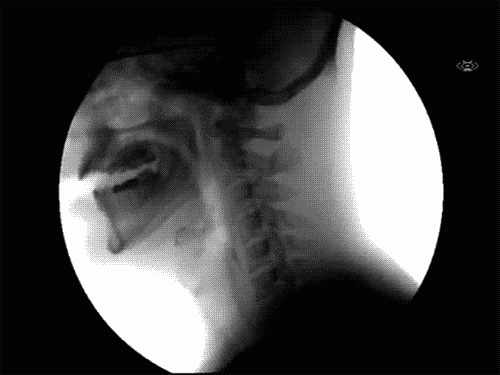

Πως το νερό μεταφέρεται από το στόμα στον λαιμό